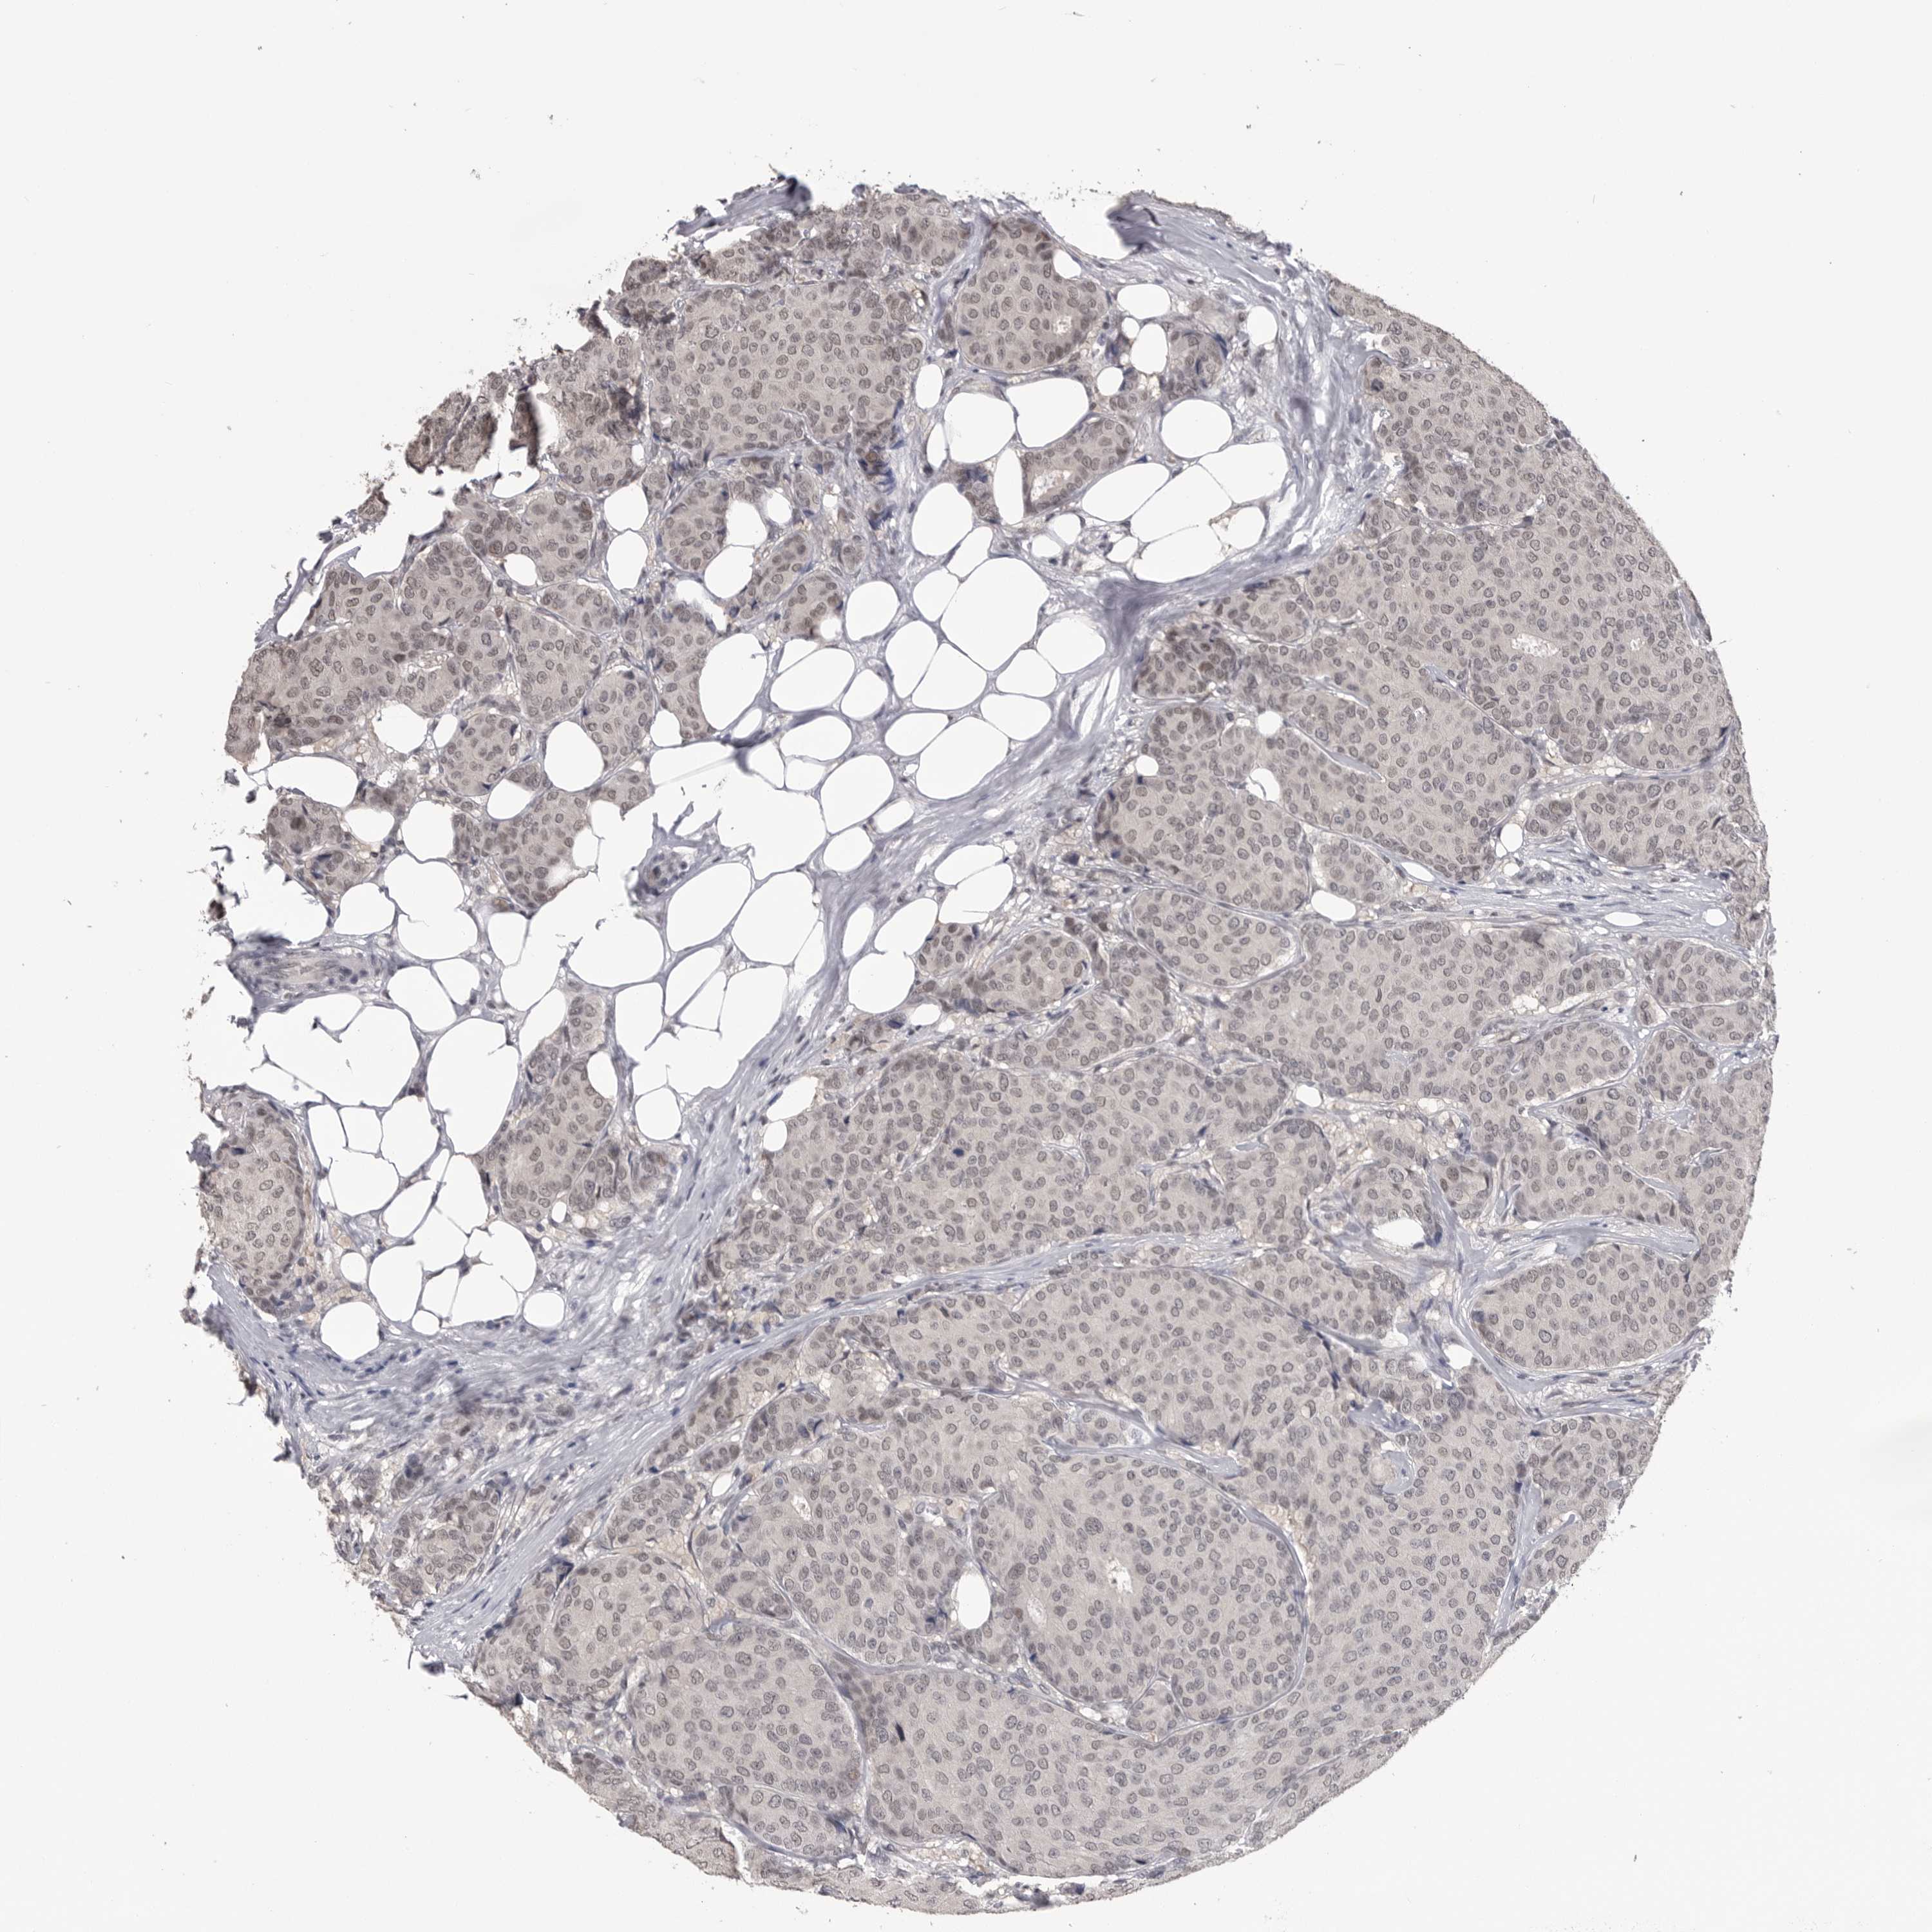

CANCER BREAST CANCER Show tissue menu

BRCA TCGA BRCA VALIDATION PROTEIN EXPRESSION